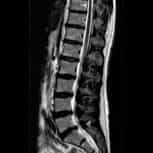

我們是一家位於西班牙巴塞隆納的國際專科醫療中心,不設分院,專注於精準且高品質的醫療照護。我們採用微創手術從病因治療Arnold-Chiari I型症候群、特發性脊髓空洞症與脊柱側彎等相關疾病,致力於為來自世界各地的患者帶來更安全、更有效的治療選擇。